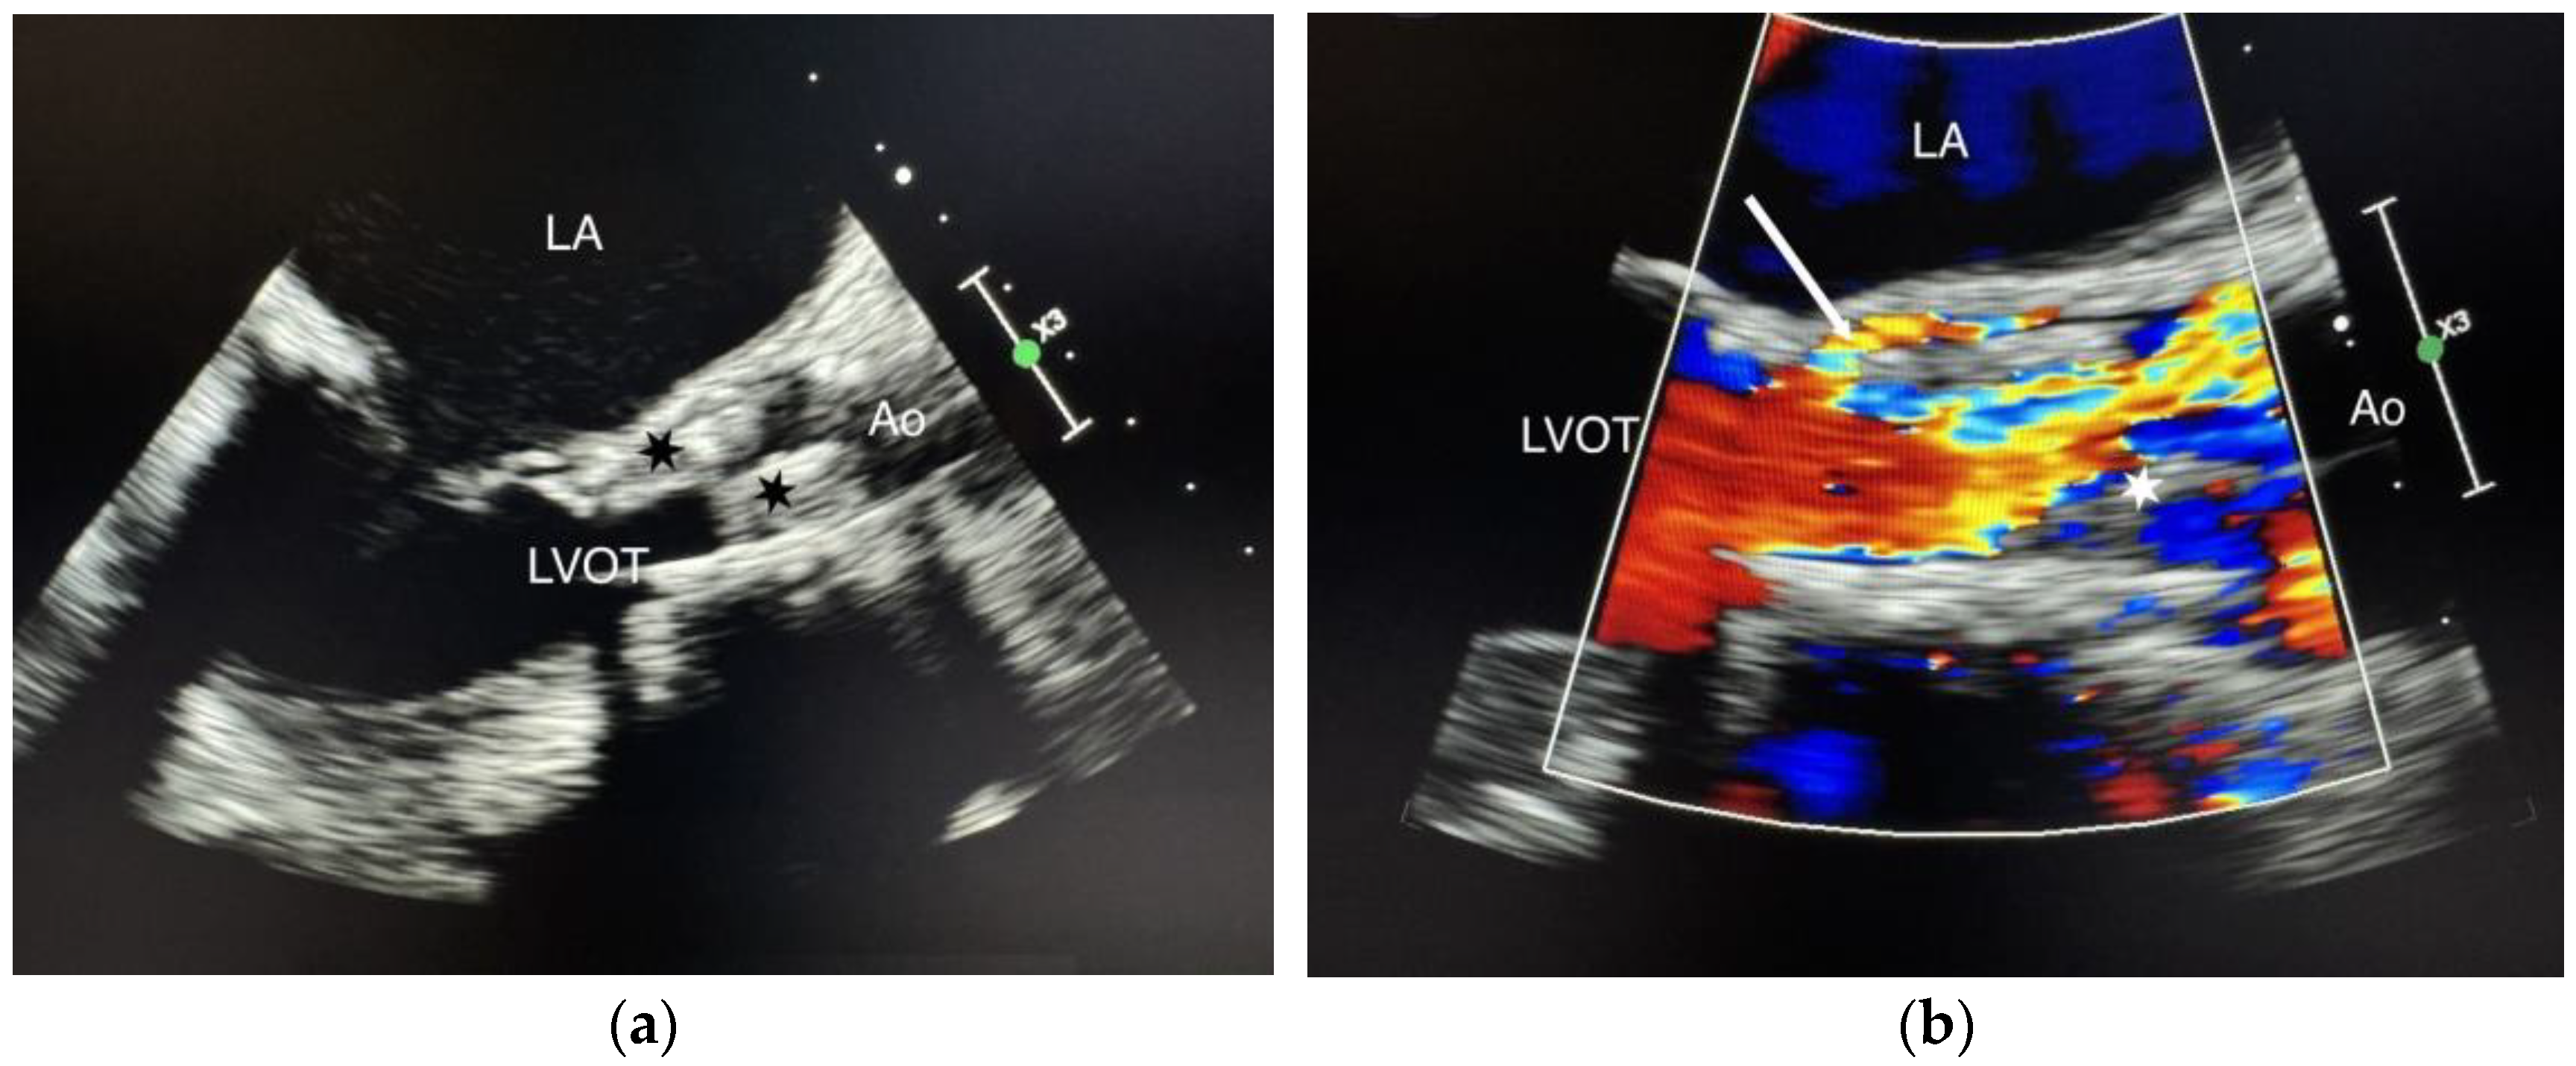

We present the case of a 75-year-old female patient, with multiple cardiovascular comorbidities, admitted to the hospital due to deterioration of her general condition. She presented with fever, asthenia, anorexia, and loss of mobility. Ten months prior to her admission, she underwent a TAVI with a self-expanding prosthetic valve (Navitor, 27 mm, Abbott Cardiovascular, Abbott Park, IL, USA). Blood cultures were positive for a multi-sensitive Enterococcus faecalis. Transesophageal echocardiography (TEE) demonstrated a 2 cm mobile mass on the aortic prosthesis leaflets, with a mean gradient of 49 mmHg and a normal left ventricle ejection fraction. Intravenous antibiotic therapy with amoxicillin-clavulanate plus ceftriaxone was initiated. One month later, TEE showed no change in the vegetation size or the mean transvalvular gradient (Figure 1a,b).

Figure 1.

(a) Standard TEE showing the vegetations. Cusp enlargement and vegetations (black stars); (b) Color Doppler TEE demonstrating paravalvular regurgitation. Vegetation (white star), paravalvular regurgitation (white arrow), LA (left atrium), LVOT (left ventricular outflow tract), Ao (aorta).